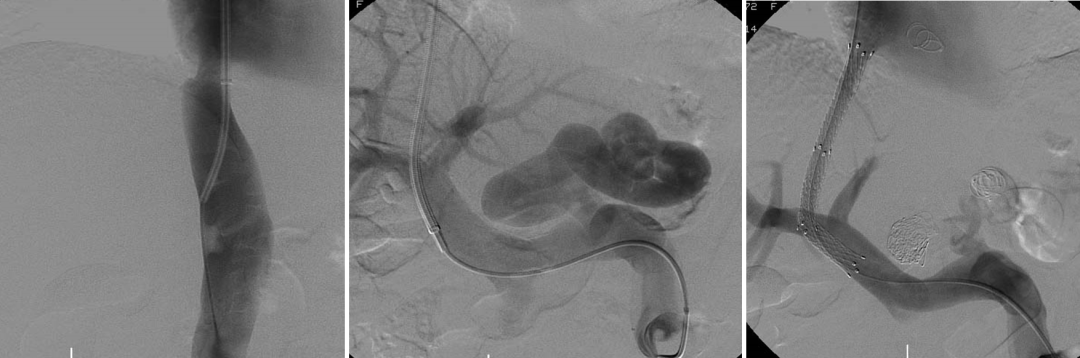

布加综合征(BCS)

对肝静脉闭塞型,直接穿刺下腔静脉建立 DIPS 通道;

对下腔静脉+肝静脉联合闭塞,先置入下腔静脉支架,再通过其作为“桥梁”完成 TIPS;

曾有一例19岁少女,每日需放腹水2000ml,术后当天腹水完全消退,疗效极为显著。

DIPSS-肝静脉闭塞(XJD)

肝静脉闭塞型

下腔静脉型合并消化道出血

下腔静脉型